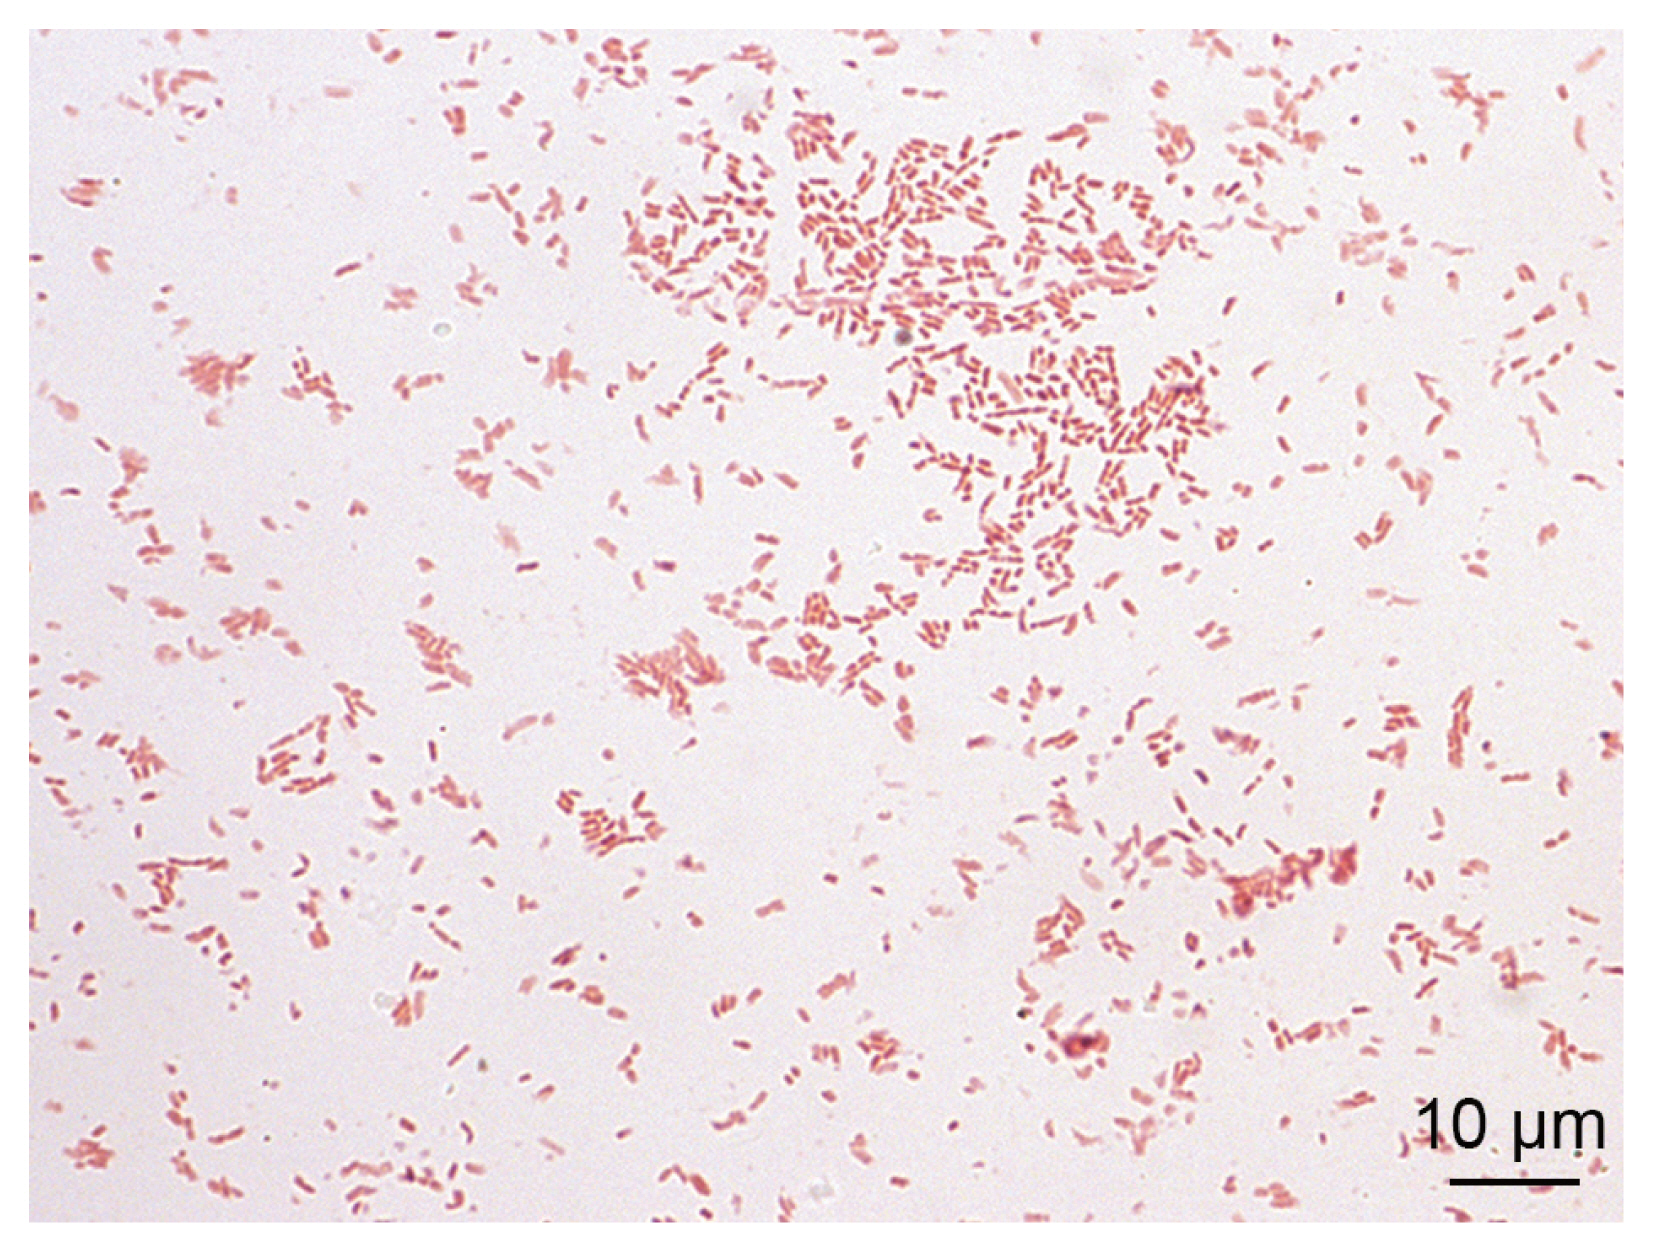

The blood cultures drawn on admission were sterile. However, of the 2 blood culture sets drawn after the second wound debridement, one anaerobic bottle was reported positive by the BD BACTEC FX blood culture system (Becton Dickinson), and Gram staining revealed Gram-negative rods (Fig. 2). Identification of bacteria directly from positive blood culture using matrix-assisted laser desorption/ionization time-of-flight mass spectrometry (MALDI-TOF MS) (Bruker Daltonics, Server version 4.1.70 (PYTH) 48 2016-10-26_15-05-35, Billerica, Massachusetts, USA) [9] was not successful. Subculturing resulted in the growth of colonies with a yellowish pigment on Columbia and chocolate agar (Fig. 3) after 18 hr of incubation. No growth was observed on anaerobically incubated growth media. The identification of bacteria by MALDI-TOF MS was unsuccessful also from subculture. The strain was identified as Ignatzschineria sp. by partial (320 bp long region) 16S ribosomal ribonucleic acid (16S rRNA) gene sequencing [10]. By sequencing a longer 1,462 bp region of the 16S rRNA gene [11], the strain was identified as Ignatzschineria larvae with an identity match of 99.9%. The nucleotide sequence was deposited in the GenBank database under the accession number MW420873. The identity match with the most closely related species was 99.2% for Ignatzschineria ureiclastica and 98.5% for Ignatzschineria indica (Fig. 4). Testing of antibiotic susceptibility was done using Etests (Liofilchem, Roseto degli Abruzzi, Italy or bioMerieux, Marcy-l’Étoile, France). The isolated strain of I. larvae was reported susceptible to piperacillin-tazobactam, ceftazidime, ciprofloxacin, and imipenem considering pharmacodynamic/pharmacokinetic (non-species related) European Committee on Antimicrobial Susceptibility Testing (EUCAST) Clinical breakpoints [12].